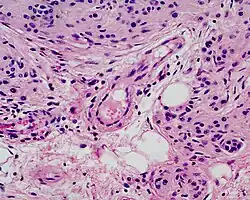

Microscopically, congenital melanocytic nevi appear similar to acquired nevi with two notable exceptions. For the congenital nevus, the neval cells are found deeper into the dermis. Also, the deeper nevus cells can be found along with neurovascular bundles, with both surrounding hair follicles, sebaceous glands, and subcutaneous fat. Such annexes and the Subcutaneous tissue can also be hypoplasic or, conversely, present aspects of hamartoma.